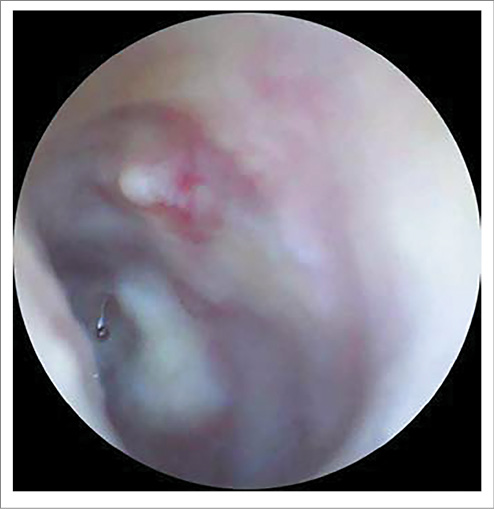

AS – околоушная, заушная область не изменена, при пальпации безболезненна. При отоскопии: наружный слуховой проход широкий, свободный, БП утолщена, местами гиперемирована, в передних отделах визуализируется центральная перфорация диаметром 2 мм, при выполнении пробы Вальсальвы из перфорации поступает скудное гнойное отделяемое (рис. 2).

Рис. 2. Отоскопическая картина слева при поступлении: БП утолщена, местами гиперемирована, в передних отделах визуализируется центральная перфорация диаметром 2 мм.